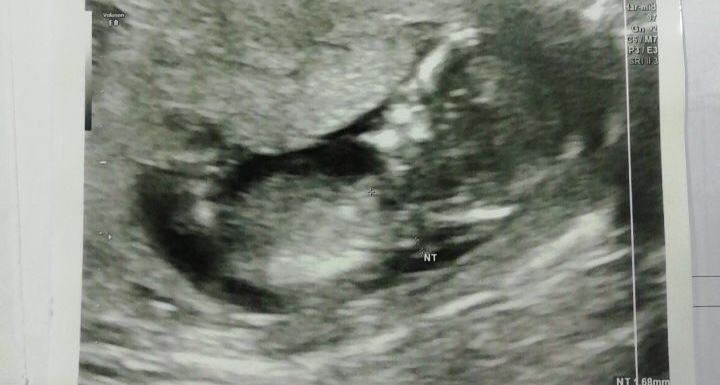

shekiba عضویت: 1398/04/16 تعداد پست: 5163 عزیزم شرمنده تهران نیستم!!عکس سونو ان تی رومیزاری خدایا هزار مرتبه شکرت

مهرزادmah مدیر استارتر عضویت: 1397/03/19 تعداد پست: 1095 عزیزم شرمنده تهران نیستم!!عکس سونو ان تی رومیزاری من اگر نيك يا بدم... تو برو خود را باش

مهرزادmah مدیر استارتر عضویت: 1397/03/19 تعداد پست: 1095 خود عکس کنجدتو بزار گلم من اگر نيك يا بدم... تو برو خود را باش